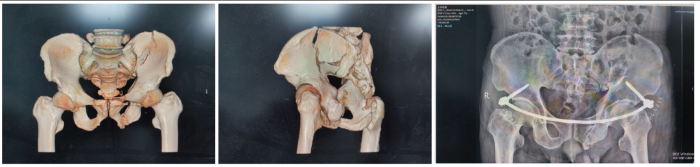

督导过程中,其中一例骨盆骨折患者采取了前环INFIX内固定术,此为骨科一病区开展的第一例前环INFIX内固定术。9月17日为术后的第12天,患者已床上坐起活动,准备隔日出院。

前环INFIX内固定术是一种用于骨盆前环的皮下内固定技术,可视为“内置的外固定架”,适用于固定耻骨联合分离和耻骨支骨折。其优点:1. 避免了传统外固定架针道感染、护理不便的问题;2.比放置于表面的外固定架更舒适,允许患者坐立和侧卧;3. 比开放切开放置钢板创伤小。缺点:术后可能感到腹部有异物感,通常在骨折愈合后需要二次手术取出内固定物。